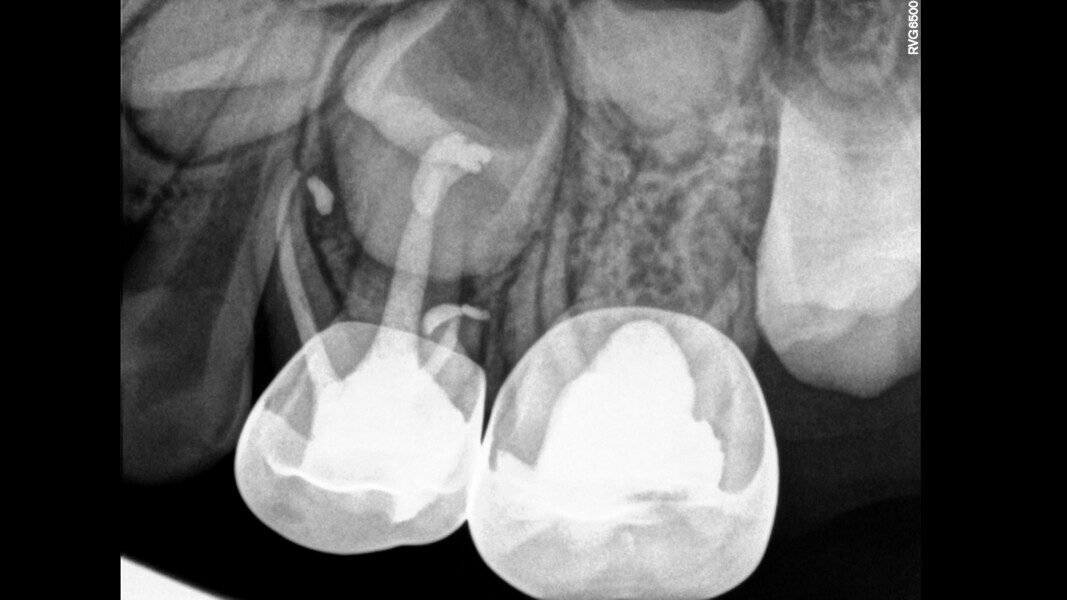

Case 2 (Figs. 5–9)

This male patient was 6 years and 7 months old and presented with severe tooth decay on the mandibular left first primary molar without any symptoms of pain. He experienced slight discomfort to percussion and palpation of the buccal gingiva. A buccal abscess and no mobility were observed. The radiograph showed a large area of interradicular bone loss. The tooth was diagnosed with pulp necrosis and an asymptomatic apical abscess. Pulpectomy was performed, and at a second appointment, a stainless-steel crown was placed upon confirming absence of signs or symptoms of disease. At the 14-month recall, no clinical pathology was detected and a normal eruptive process of the permanent premolars was observed in spite of the extrusion of the obturation material.